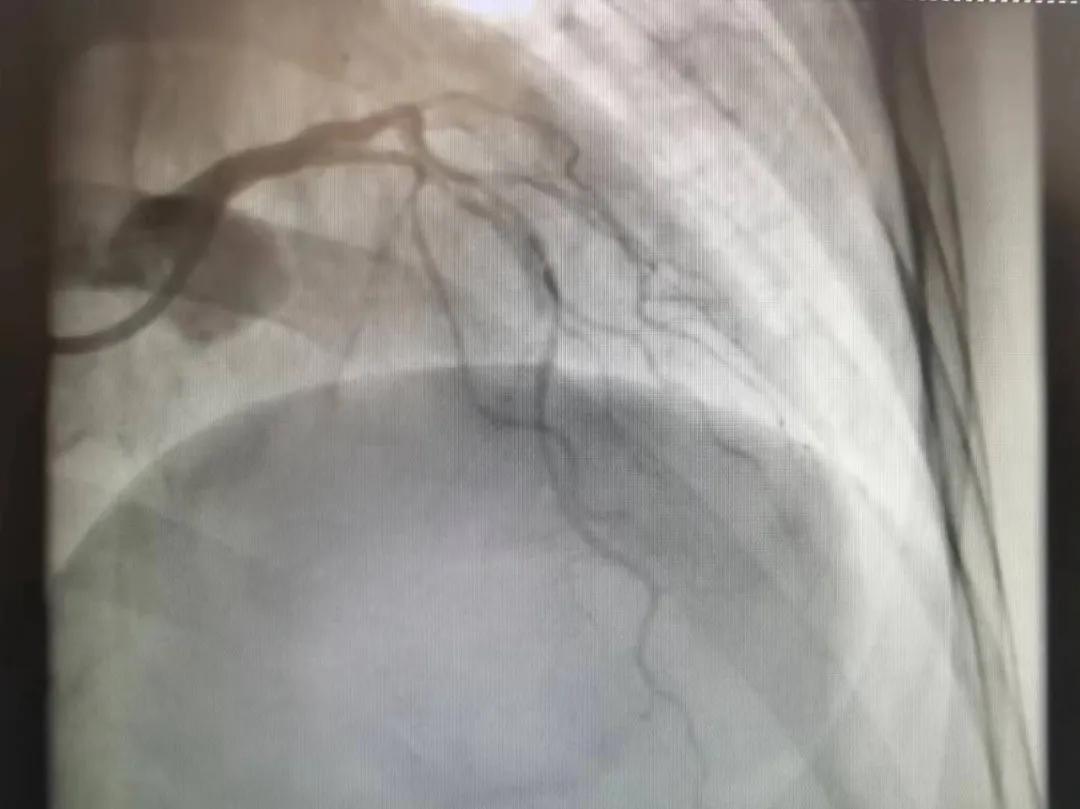

病人是位六十多歲的女性患者,有長期高血壓病史,1個月前開始出現(xiàn)胸悶胸痛,口服藥物治療效果不佳,經(jīng)朋友介紹,來到市二院心血管內(nèi)科。入院后完善冠狀動脈造影提示:前降支全程彌漫性狹窄伴鈣化,最重95%,回旋支狹窄約85%,右冠脈全程狹窄伴鈣化,最重60%。血管內(nèi)超聲顯示右冠脈開口面積3.36mm²,可見環(huán)形鈣化,考慮患者病變程度重、鈣化明顯,常規(guī)器械無法實(shí)現(xiàn)病變的良好預(yù)處理,且有很高的冠脈穿孔、血管夾層的風(fēng)險。

術(shù)前

王瑾院長和李慧新主任帶領(lǐng)介入團(tuán)隊(duì)充分評估,決定行前降支冠狀動脈鈣化病變旋磨術(shù),術(shù)中應(yīng)用1.5mm旋磨頭,以15萬-17萬轉(zhuǎn)/分速度共對病變旋磨3次,累計(jì)旋磨時間60秒,后復(fù)查造影示鈣化明顯減輕,為后續(xù)操作創(chuàng)造了良好條件,隨后應(yīng)用預(yù)擴(kuò)張球囊、切割球囊再次處理病變,并順利植入支架1枚,復(fù)查造影顯示支架膨脹及貼壁良好,無夾層、血腫、慢血流等情況,手術(shù)順利完成?;颊咝g(shù)后無不適,胸悶、胸痛癥狀明顯緩解,順利出院。

術(shù)后